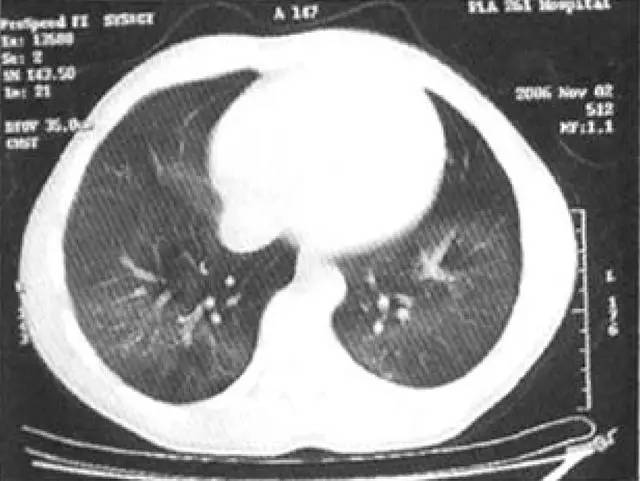

基本病史:患者,男,19 岁,间断咯血 5 年,加重 1 年,患者 5 年前因咳嗽,咳痰,痰中带血,于当地医学就诊,以肺炎治疗后症状减轻,但仍间断出血咯血症状。行胸部检查结果如下:

图 1 胸部 CT 示双下肺弥漫性磨玻璃影,呈腺泡结节样分布,最终病理诊断结果为特发性肺含铁血黄色沉着症